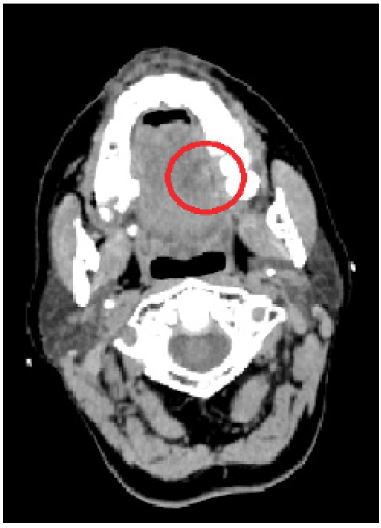

A 52-year-old woman presented to the Emergency Department due to a 3-day history of unilateral swelling of the tongue, mild fever, dysphagia and dysphonia. She had been previously diagnosed with stomatitis by a General Practitioner and received prednisolone per os without improvement. The patient did not report any recent trauma, oral infection or dental procedure, was a non-smoker and had no history of alcohol consumption. Her medical history was unremarkable with the exception of an allergic reaction to amoxicillin/clavulanic acid and trimethoprim/sulfamethoxazole. The examination of the oral cavity showed obvious lingual swelling located on the left middle third of the tongue (Figure 1). Palpation or movement of the tongue caused severe pain to the patient. Her oral hygiene was poor but there was no sign of odontogenic inflammation. Rigid fiberoptic laryngoscopy revealed no pathology of the larynx or the base of the tongue. The laboratory tests showed leukocytosis, neutrophilia and elevated high sensitivity C- Reactive Protein (hsCRP). A Computed Tomography (CT) was performed and revealed a heterogeneous lesion with hypoattenuating borders in the left middle third of the tongue (Figure 2). The patient was hospitalized in the ENT Department and treated with clindamycin i.v. and anti-inflammatory agents, empirically. Drainage of the abscess was performed with a sublingual incision under Total Intravenous Anesthesia (TIVA). The pus culture revealed no bacteria. All the symptoms subsided within 48 hours. The patient was discharged after four days and advised to complete treatment with clindamycin per os.

Figure 2: Cervical CT scan: lingual abscess indicated by the heterogeneous lesion with hypoattenuating borders (red circle).